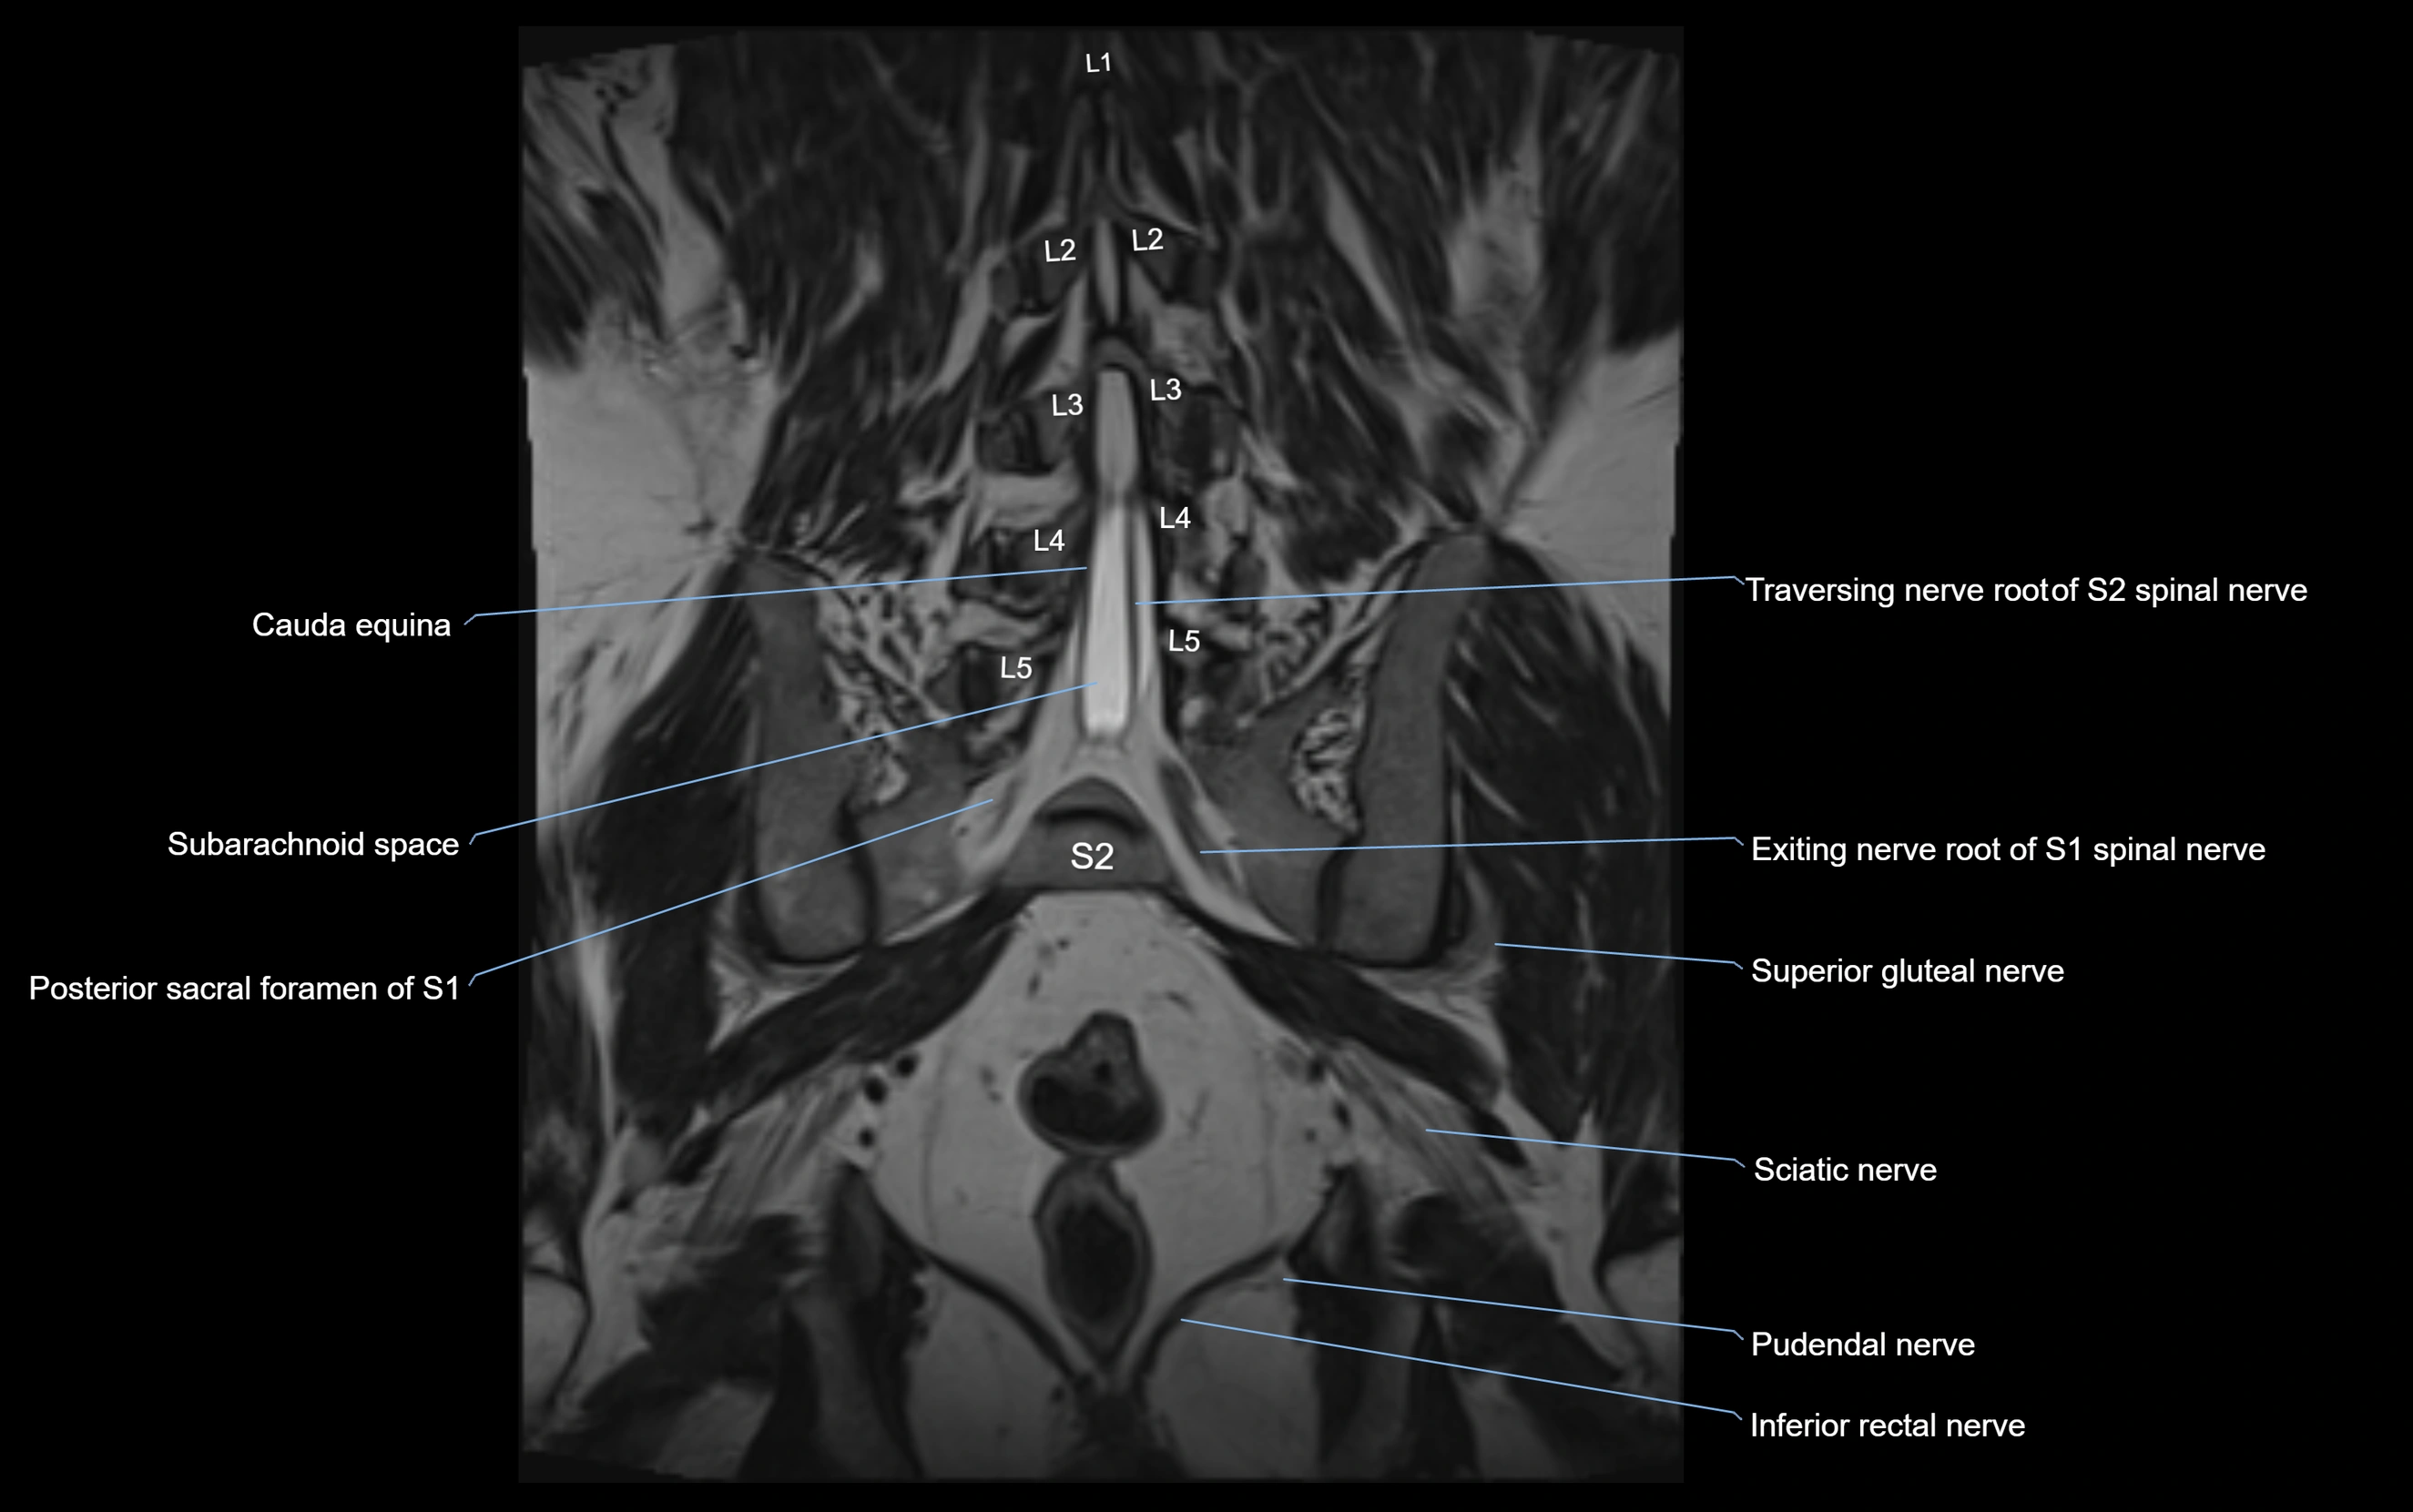

MRI Appearance

T1-weighted images:

• Nerve appears as a very thin low-to-intermediate signal intensity structure

• Surrounded by bright fat, aiding visualization

T2-weighted images:

• Nerve shows intermediate to mildly hyperintense signal compared to muscle

• Pathological involvement appears brighter

STIR (Short Tau Inversion Recovery):

• Normal nerve appears dark

• Inflamed or entrapped nerve appears bright hyperintense

T1 Fat-Sat Post-Contrast:

• Normal nerve enhances minimally

• Pathologic nerve (neuritis, entrapment, tumor infiltration) shows focal or diffuse enhancement

3D T2 SPACE / CISS:

• Nerve appears intermediate to mildly hyperintense compared to muscle

• Surrounded by bright fat or CSF, improving visualization

• Best sequence for mapping small pelvic nerves such as the anococcygeal